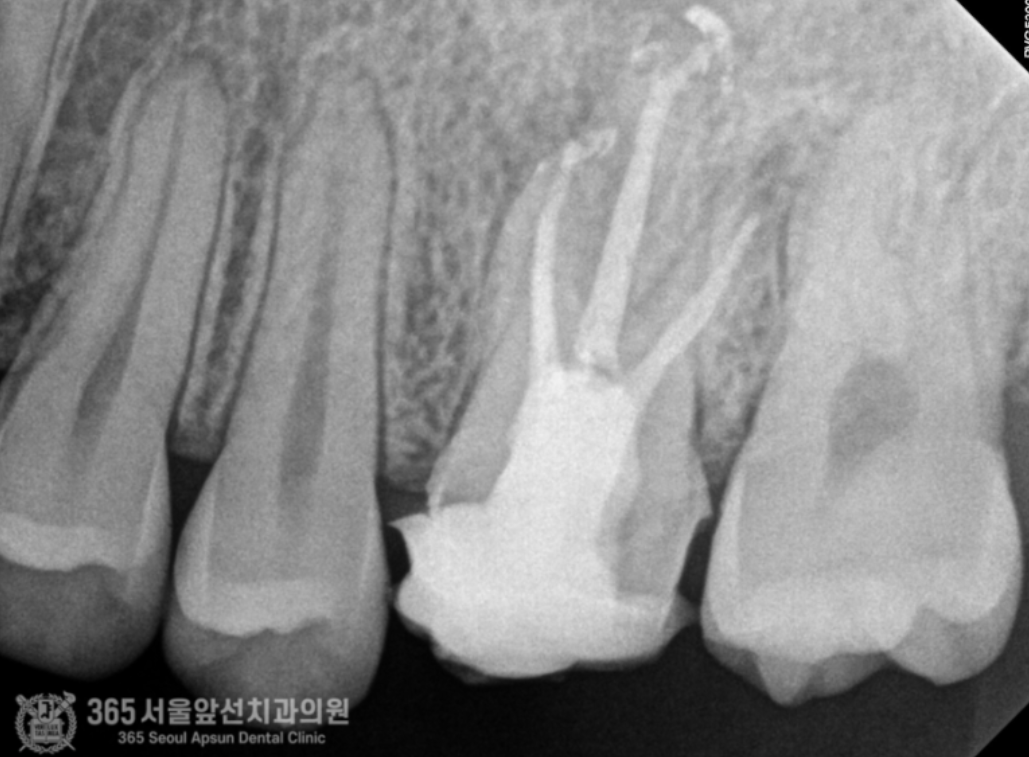

안녕하세요. 미추홀구치과 365서울앞선치과의원입니다. 오늘은 재신경치료 증례를 살펴보겠습니다. 왼쪽 위쪽의 치아가 아프다는 불편감으로 환자분께서 내원하셨습니다. 너무 아파서 잠을 제대로 못 주무셨다고 하십니다. 수면부족으로 많이 예민해지신 상태셨습니다 ㅠㅠ 구강 내를 관찰하며 검사를 시작합니다. "아~ 해보세요" 전반적으로 깨끗한 상태셨지만 기존에 치료받았던 치아가 통증의 원인으로 의심이 되는 상황입니다. 촬영일시 : 2024.06.21. 내원 당시 파노라마 엑스레인 사진입니다. 자세하고 정확한 검사를 위해 작은 엑스레이 사진을 한장 촬영했습니다. 촬영일시 : 2024.06.21. 과거 타병원에서 신경치료 및 크라운 치료를 받으신게 관찰됩니다. 과거 신경치료를 받으셨던 치아 뿌리 끝에 염증이 생겼네요 ㅠㅠ 신경치료의 충전 상태가 짧은 것도 관찰됩니다. 이런 경우, 환자분의 나이 및 건강상태 그리고 치아의 치료상태 등을 종합적으로 판단하여 치아를 보존할지 아니면 발치하고 임플란트로 계획을 세울지 결정해야합니다. 해당 치아의 경우 치아의 상태는 좋지 않았지만 기존 신경치료의 충전 상태가 그다지 좋지 않은 상황이라 재신경치료를 통해 한 번 더 치아를 살려서 써보는 것이 가능한 상황으로 보였습니다. 하지만 재신경치료의 경우 일반적인 신경치료에 비해 난이도가 높고 성공율이 떨어지는 것도 사실입니다. 그만큼 최선을 다해도 쉽지 않은 것이 재신경치료인데요~ 다행히 위 환자분께서는 성공적으로 재신경치료를 마무리할 수 있었습니다 ㅎㅎ 촬영일시 : 2024.06.21. 재신경 치료를 통해 깔끔하게 충전된 모습이 엑스레이상에서 관찰됩니다. 쉽지 않은 치료도 최선을 다하는 마음을 갖는다면 좋은 결과를 얻을 수 있다는 것을 느끼게 해준 증례였습니다. 오늘도 감사합니다 항상 최선을 다하는 치과의사가 되겠습니다 ^^ [ 치료기간: 2024년 6월21일 ] ※ 365서울앞선치과의원의 모든 포스팅은 각 진료과 의료진이 직접 작성합니다. 365서울앞선치과의원 블로그의 임상 케이스 게시물은 환자분께 의학적으로 정확하고 상세한 정보를 드리기 위해 각 진료과 의료진이 직접 작성하며, 모든 증례 사진은 본원 의료진이 직접 시술한 증례를 촬영한 것으로, 의료법 제23조, 제56조에 의거하며 환자분의 동의를 얻어 포스팅에 사용하였습니다. 또한 해당 케이스는 본 환자분의 치료 결과이며, 환자 상태에 따라 치료의 결과는 달라질 수 있습니다. |